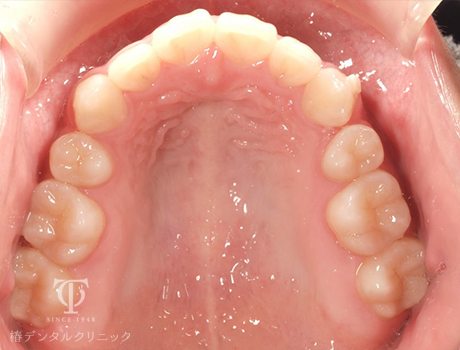

マウスピース装着前

Case01

-

- 症状

- 前歯の歯並びがずれてきた

- 治療期間

- 約5か月

- 治療費用

- 330,000円

以前全顎矯正をしていて後戻りをおこしてしまった患者様です。軽度の叢生のため、マウスピース矯正をおこないました。